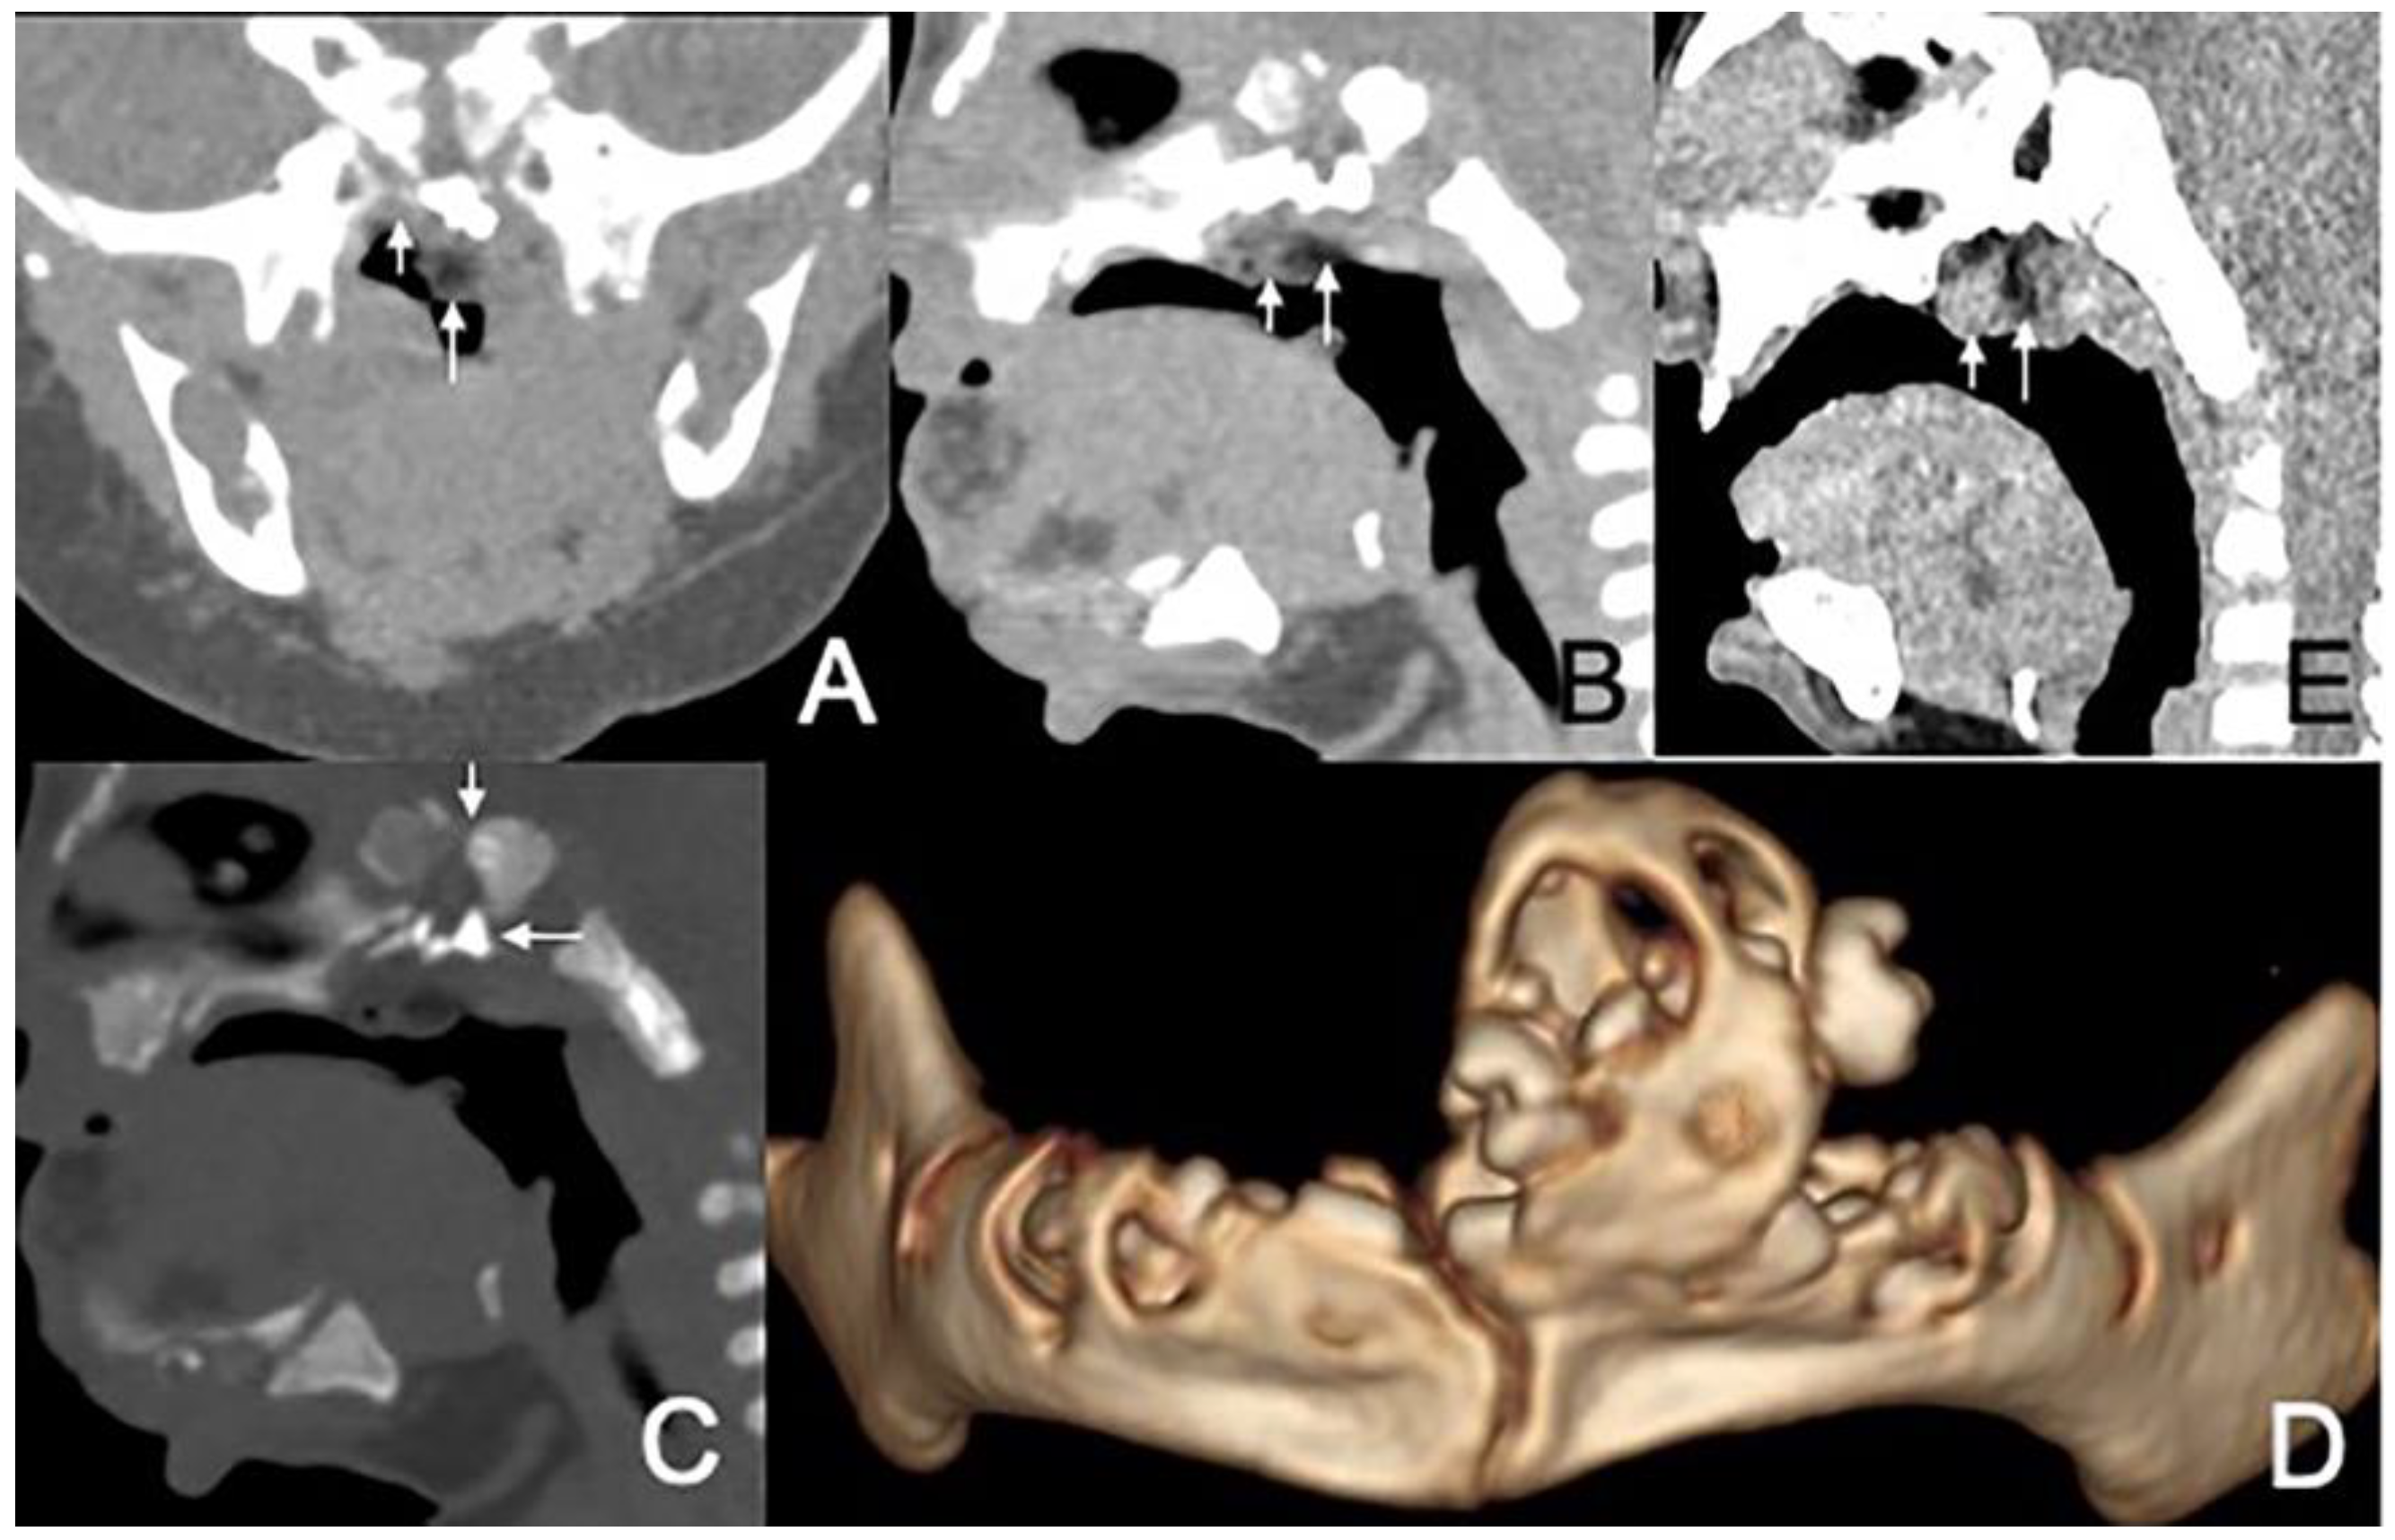

Figure 1. CT and MRI of a 2-month and 17-day girl presenting shortly after birth with dyspnea and inspiratory stridor. (A) Axial CT, displayed in the soft-tissue window, shows the soft palate mass protruding to the left nasal cavity and blocking the bilateral choanae to be of predominantly low attenuation, containing an irregular moderate-attenuation stalk. (B) Axial, postcontrast, T1W-SPIR MRI shows that the lesion’s stalk is slightly enhanced (arrows), but the rest of the lesion is not enhanced. (C) Sagittal T1-weighted MRI shows an irregular mass in the soft palate and left nasal cavity that mainly has a high-signal (short arrow) with an irregular low-signal central stalk (long arrow). (D) Coronal CT, displayed in the bone window, shows the soft palate mass associated with the cleft palate (arrow).

The size of masses varied from 0.6 to 4.3 cm. There were 11 (78.6%) cases with the largest diameter of the mass greater than 2 cm. The shapes of the masses were varied. Eleven (78.6%) cases presented with typical pedicled masses containing fat and a central core of soft tissue, including sausage-like masses in five (35.7%) cases, tongue-like masses in four (28.6%) cases, and pear-like masses in two (14.3%) cases. Of the eight patients who underwent MRI scans, there were five (62.5%) patients whose masses had high signal intensity on T1-weighted and T2-weighted sequences with a low-signal central core whose signal intensities were similar to those of muscles. The high signal intensities on all sequences were similar to the fat signals and attenuated by fat suppression. The central core demonstrated mild enhancement following intravenous gadolinium administration, while the surrounding components of the fat signals demonstrated no enhancement in one case (Figure 1). There was no reduced diffusion of the five patients who underwent DWI. Via CT, there were 10 (83.3%) cases whose masses appeared as well-circumscribed fat attenuation masses surrounding a central core of soft tissue. The central core was mildly enhanced following intravenous iodixanol administration, but the fat components were not enhanced in one case (Figure 2). There were five patients who received both MRI and CT.

3.3. Associated Malformation

Six (42.9%) patients had other abnormalities. Five of them were incidental findings within the imaging scope of their investigations and one was in the other area. One infant had ossicular chain disruption showing the absence of the left stapes head and part of stapes arch (Figure 6), one had a cystic lesion of liver by abdomen ultrasound, one had frontal midline lipoma (Figure 3), one had a cleft palate (Figure 1) and pectus excavatum, one had a right first branchial fistula, and one had a cleft palate and ameloblastic fibro-odontoma of the mandible as well as highly suspicious ectopic teeth and the remnant of craniopharyngeal canal development (Figure 5).

Upon MRI, most of the masses were found to have heterogeneous high signal intensity on T1-weighted and T2-weighted sequences with a low-signal central core whose signal intensities were similar to those of muscles. The high signal intensities on all sequences were similar to the fat signals and attenuated by fat suppression. The central core demonstrated mild enhancement following intravenous gadolinium administration, while the surrounding components of the fat signals demonstrated no enhancement. The central core helps us trace the origin of the mass, which is important for the choice of surgical method. Characteristic imaging features on CT include well-circumscribed masses containing fat and linear soft tissue–density components centrally that correspond to the fibrovascular stalk [2]. The central core was mildly enhanced, as expected for fibrous tissue, but the fat components were not [23]. These findings corresponded well with the MRI and CT features previously described [24,25]. Intracranial or intraspinal extension was not found in any of the lesions in the present study, which was consistent with existing reports.